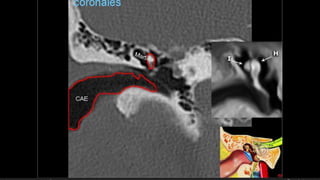

Evaluación Imagenologica

• #38 Izqu. AXIAL-- fxLongitudinal perdonan la capsula otica (laberinto oseo) Centro AXIAL fx trnasversa lascuales tperdonan el lab erinto oseo Dere: MIXTA – tmp perdona